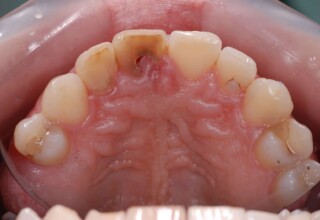

Dark root canal teeth

A rare case of dark root canal teeth with additional external absorption on the central incisor. After removal of the affected tissues of the central incisor, the tooth could not be directly bleached because of the soft tissue contact. The tooth was initially restored to provide the original tooth form, then it was bleached and the restoration was finalized.

Initial appearance